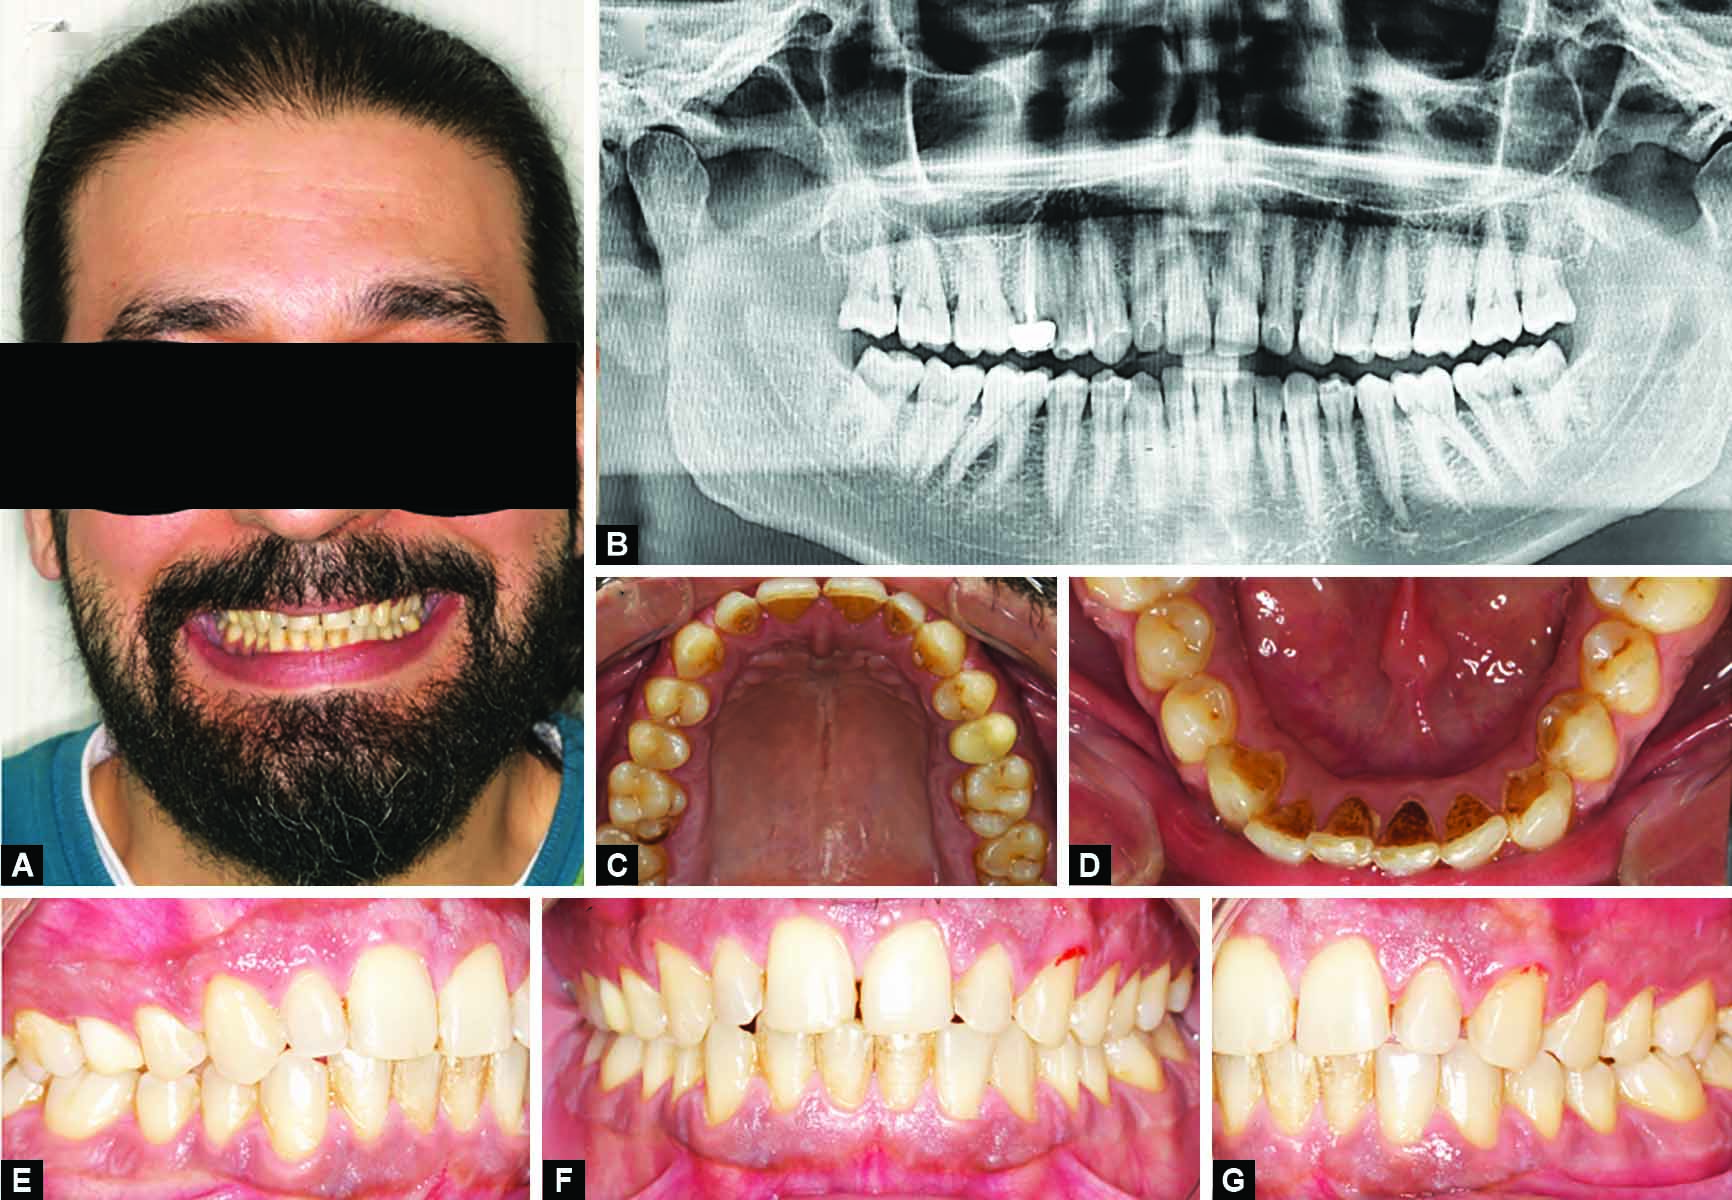

Extraoral examination revealed an asymmetrical facial proportion vertically, with the nose deviating to the right (Fig. 1A). Intraoral examination revealed heavily stained teeth (Figs 1B to G). Orthodontic treatment was recommended for the patient to correct the curve of Spee prior to performing veneers preparation and cementation to reduce the amount of tooth structure removal. However, the patient rejected this option.

Figs 1A to G: Patient preoperative photos: (A) Smile view showing unproportioned dentition that is resistant to vital bleaching; (B) Preoperative panoramic radiograph; (C) Upper occlusal view photo; (D) Lower occlusal view photo; (E) Right lateral photo at maximal intercuspation; (F) Frontal retracted photo at maximal intercuspation; (G) Left lateral photo at maximal intercuspation